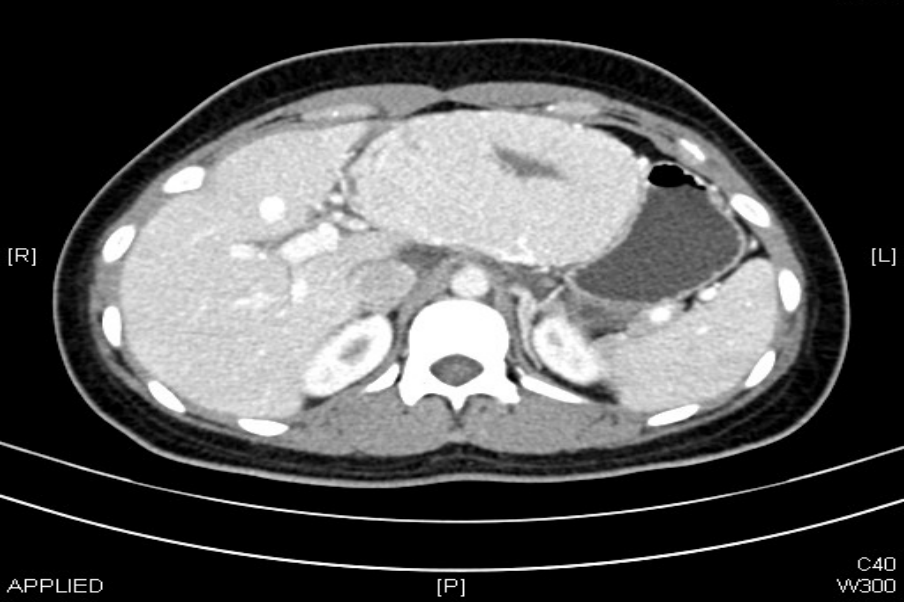

体检后发现左肝

居然长出了一个“大疙瘩”

直径约11cm

确诊为肝局灶性结节性增生